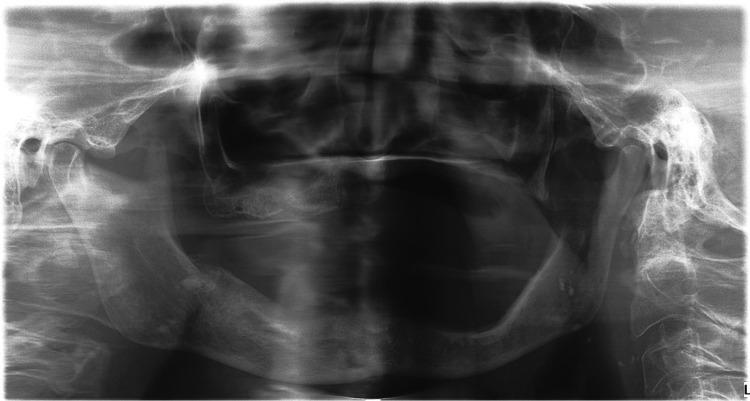

Both denosumab (DMB) and bisphosphonates (BPs), antiresorptive drugs (ARDs) used for the treatment of osteoporosis and oncological disorders, are known for their potential to cause medication-related osteonecrosis of the jaws (MRONJ). Besides ARDs, statins were recently associated with MRONJ development, especially in patients taking higher doses of statins for a longer period of time. Here, we report a case of a female patient with osteoporosis using statins and treated with alendronate for 3 years who rapidly developed MRONJ stage III after only a single low dose of DMB. After partial maxillectomy complete healing was observed without any recurrence. We performed a literature review of cases with MRONJ triggered by a single low dose of DMB, with or without previous application of other ARDs. Only six similar cases of patients who developed MRONJ after a single low dose of DMB following previous BP therapy have been reported so far. Besides these, literature reports one patient who developed MRONJ after a single dose of DMB following romosozumab treatment and five cases developing MRONJ after a single dose of DMB even without any previous ARD treatment. We suggest that before DMB therapy is initiated, all factors predisposing to MRONJ development should be considered.

地诺单抗(DMB)和双膦酸盐(BPs)均为用于治疗骨质疏松症和肿瘤疾病的抗吸收药物(ARDs),它们因具有引发药物相关性颌骨坏死(MRONJ)的潜在风险而闻名。除ARDs外,他汀类药物最近也与MRONJ的发生有关,尤其是在长期服用高剂量他汀类药物的患者中。在此,我们报告一例患有骨质疏松症的女性患者,该患者使用他汀类药物并接受阿仑膦酸钠治疗3年,在仅接受单次低剂量DMB治疗后迅速发展为III期MRONJ。在部分上颌骨切除术后,观察到完全愈合且无任何复发。我们对由单次低剂量DMB引发的MRONJ病例进行了文献综述,无论之前是否应用过其他ARDs。到目前为止,仅报道了6例在先前接受BP治疗后单次低剂量DMB引发MRONJ的类似病例。除此之外,文献报道了1例在接受罗莫单抗治疗后单次剂量DMB引发MRONJ的患者,以及5例即使之前未接受任何ARD治疗单次剂量DMB后引发MRONJ的病例。我们建议在开始DMB治疗之前,应考虑所有易导致MRONJ发生的因素。